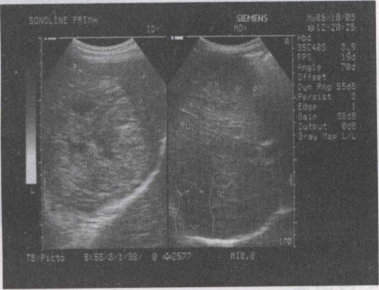

48.男,57岁,慢性乙肝多年,现上腹痛,食欲缺乏,AFP>500,结合超声声像图,诊断为()